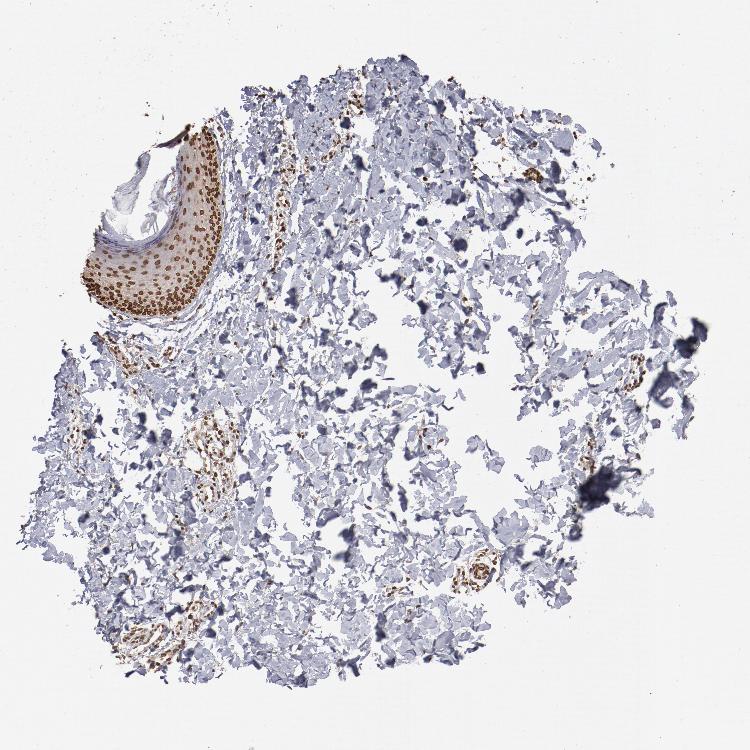

SKIN 1 - Antibody stainingi

Antibody staining in the annotated cell types in the current human tissue is reported as not detected, low, medium, or high, based on conventional immunohistochemistry profiling in selected tissues. This score is based on the combination of the staining intensity and fraction of stained cells.

Each image is clickable and will lead to virtual microscopy that enables deeper exploration of all samples and also displays staining intensity scores, fraction scores and subcellular localization as well as patient and tissue information for each sample.

Antibody HPA002891Antibody CAB003765Antibody CAB080436

Langerhans HighNot detectedHigh

Fibroblasts HighMediumHigh

Keratinocytes HighLowMedium

Melanocytes HighHighHigh